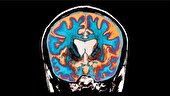

پلاسما پزشکی حوزه‌ای نوآورانه و نوظهور است که فیزیک پلاسما، علوم زیستی و پزشکی بالینی را با هم ترکیب می‌کند. در یک دیدگاه کلی‌تر، کاربرد پلاسما در پزشکی را می‌توان به دو رویکرد اصلی تقسیم کرد: اول، استفاده «غیرمستقیم» از تکنیک‌های مبتنی بر پلاسما یا پلاسمای مکمل برای درمان سطوح، مواد یا دستگاه‌ها به منظور دستیابی به ویژگی‌های خاص برای کاربردهای پزشکی ویژه و دوم، کاربرد پلاسما رو یا داخل بدن انسان یا حیوان برای تحقق اثرات درمانی بر اساس تعامل مستقیم پلاسما با بافت زنده.

پلاسما که از آن با عنوان «حالت چهارم ماده» یاد می‌شود، از دهه‌ ۱۹۶۰ در علوم فیزیک و مهندسی شناخته شده بود‌ اما ورود آن به عرصه پزشکی بسیار دیرتر و با تحولات فناورانه مهمی همراه بود. پلاسماهای غیرحرارتی یا پلاسمای سرد که قادرند در دماهای نزدیک به محیط عمل کنند، امکان تماس مستقیم با بافت‌های زنده را فراهم ساختند و نقطه آغاز پلاسماپزشکی (Plasma Medicine) شدند.